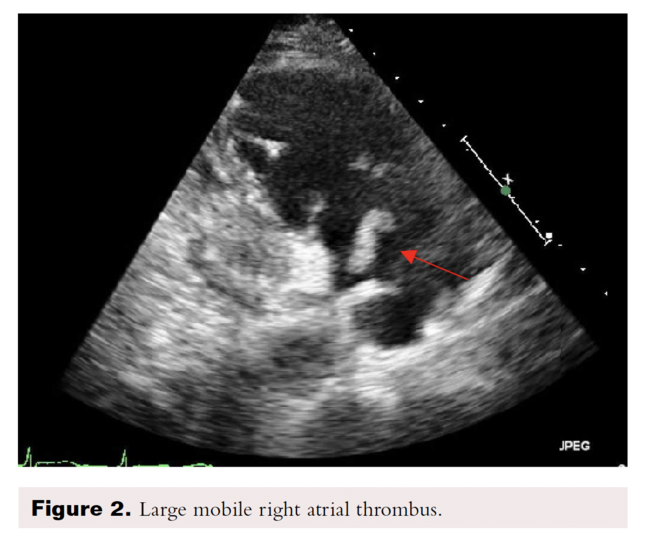

Transthoracic echocardiography showed severe dilated right chambers. There was a large, highly mobile right atrial thrombus (Figure 2), with severe systolic right ventricular dysfunction: severe tricuspid regurgitation and pulmonary artery systolic pressure of 100 mmHg (Figure 3).

Two types of RHT have been described. Type A thrombi are visualized in transit within the right cardiac cavities, morphologically serpiginous, highly mobile, and associated with PE. Type B thrombi are not mobile, formed in situ and are associated with underlying cardiac abnormalities. Based on the TTE images, this patient had a Type A thrombus.1,2,3